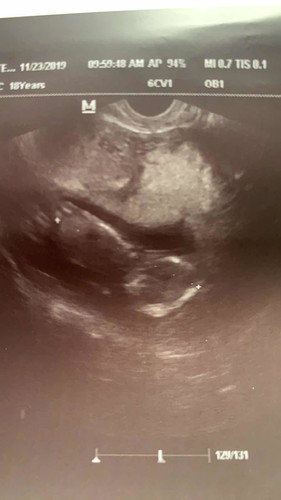

So excited to meet my little bundle of joy ..

Excited to become a mum